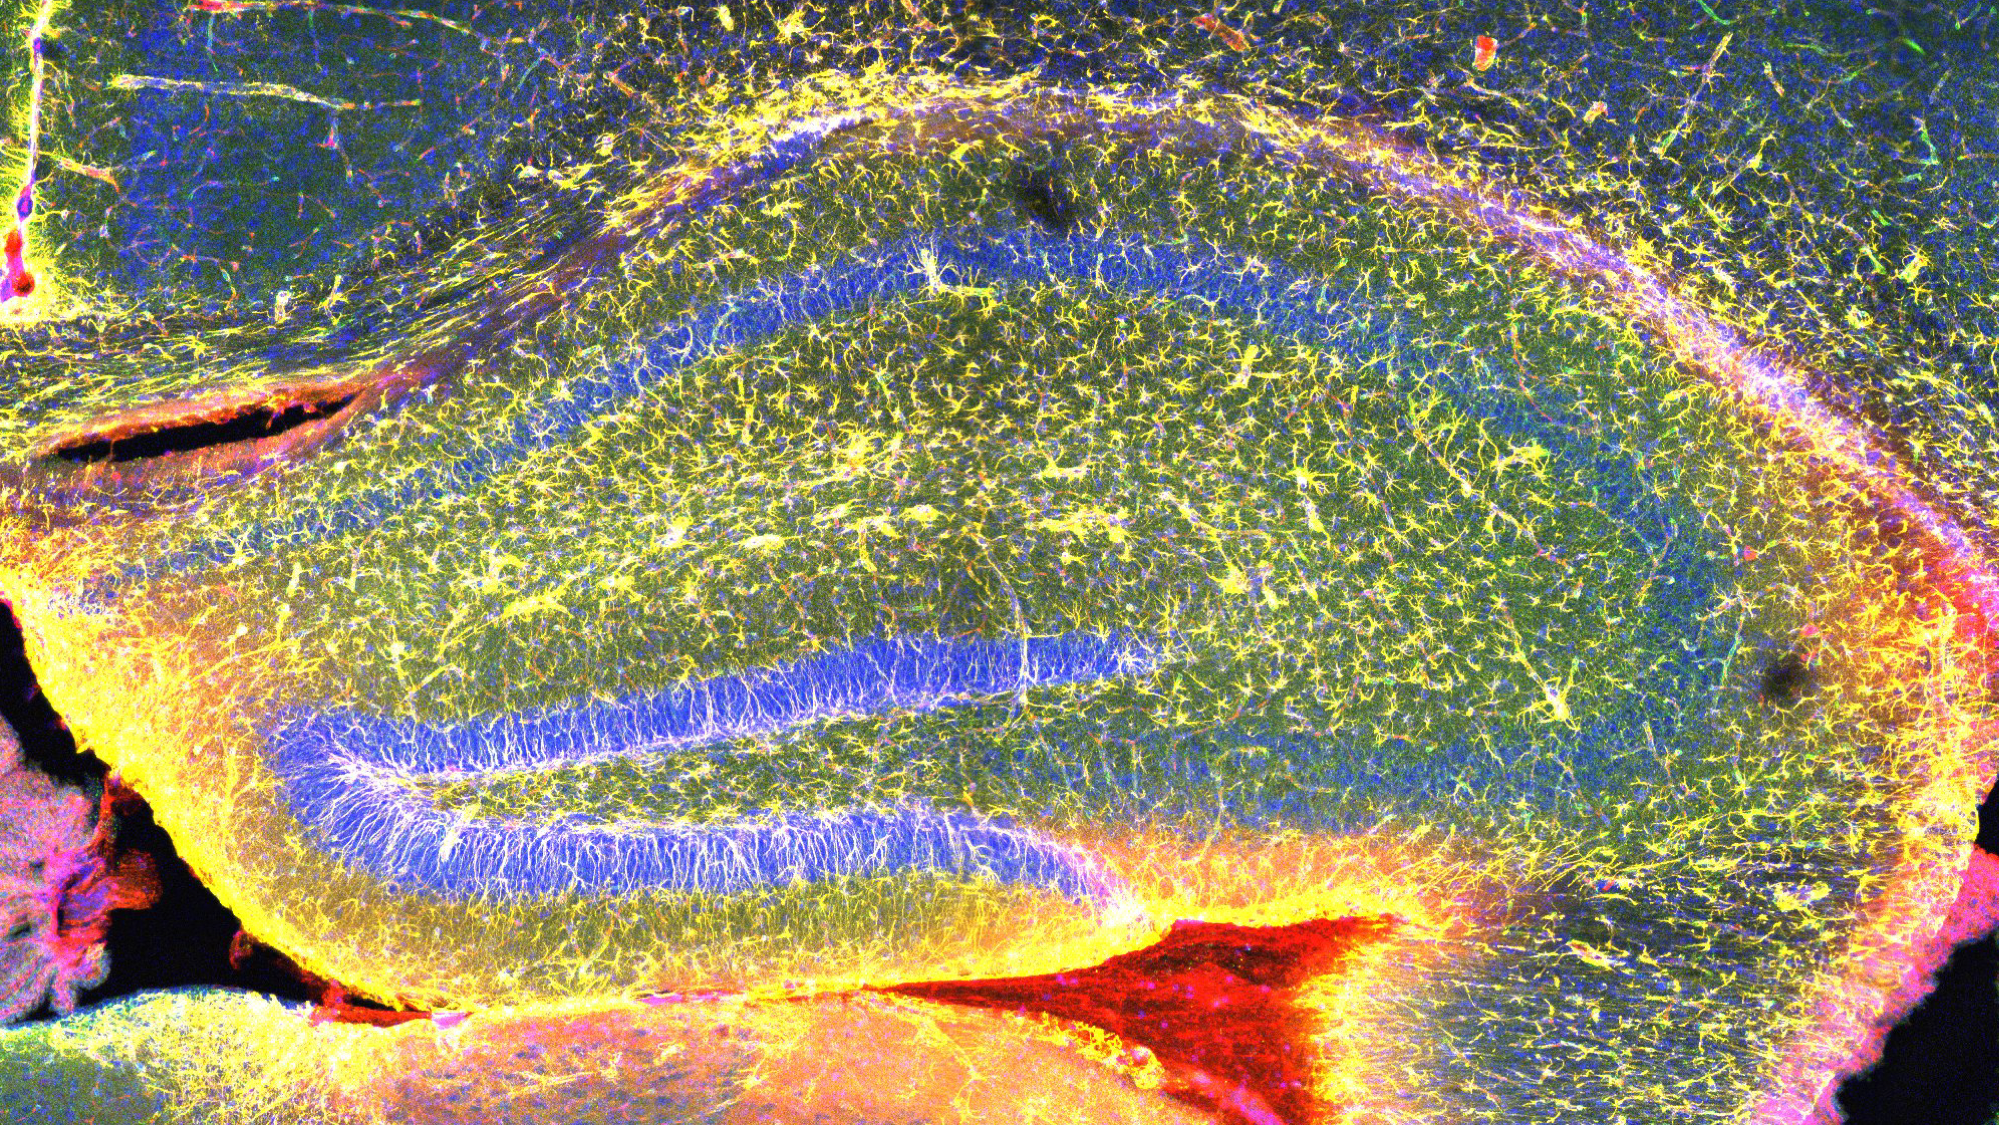

The Pedicord Lab seeks mechanistic insights into the influence of commensal microbes on host intestinal and systemic physiology and immune responses. These fundamental insights will give us a better understanding of infectious diseases, autoimmune disorders and cancer, enabling the development of new approaches to enhance therapies and combat disease. Using functional metagenomics, in vivo models, cellular immunology, transcriptomics and proteomics, we identify the cellular and molecular targets of gut microbiota-mediated modifications of host immunity. Our multi-disciplinary mechanistic approach allows us to characterise the complex interactions between the commensal microbial community, intestinal epithelium and adaptive immune cells both during homeostasis and the perturbations of disease.